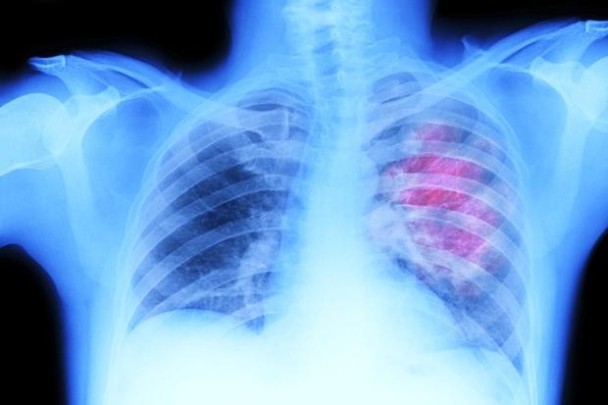

英国最新研究发现接受胸腔放射治疗 末期小细胞肺癌患者有望增加存活率

(蜘蛛网报道)英国最新研究发现,患上末期小细胞肺癌(SCLC)的患者,若接受胸腔放射治疗,有望增加存活率。

英国癌症研究学院让498名来自英国、荷兰、挪威和比利时,曾接受初步化疗并见效的SCLC患者,分别接受2星期的一般放射治疗和胸腔放射治疗。结果发现,接受胸腔放射治疗的患者,2年后有13%仍然健在,而接受一般治疗的患者,则只有3%仍然存活。

研究又发现,接受胸口放射治疗者存活半年而病情没恶化的达24%,较接受一般放射治疗的多出17%。研究人员认为胸腔放射治疗是治疗肺癌的新突破,有关研究刊登于医学期刊《刺针》。